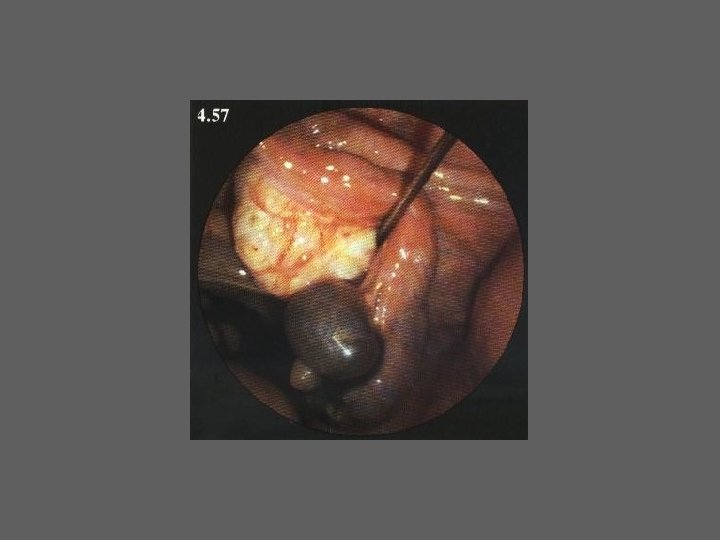

HISTEROSCOPIA - INDICAÇÕES Todas a situações em que se julgue vantajosa uma visualização completa da cavidade uterina, em particular: – Metrorragias – Dismenorreia adquirida – Infertilidade – Abortamentos de repetição e parto pré-termo – HSG anormal – DIU “perdido” – GIFT e ZIFT – Tratamento cirúrgico da patologia intracavitária: ● pólipos, miomas, septos, sinéquias, recessões endometriais ● baixos custos, reduzida morbilidade

HISTEROSCOPIA - MATERIAL CO 2 – Insuflador – Metrorragias max. 100 ml /min p < 100 mm Hg liquido (soro glicosado, dextrano, etc. ) – Fonte de luz fria – Histeroscópio (3, 5, 7 mm) – rígido ou flexível – Bainha e instrumentos cirúrgicos (pinça de biopsia, tesoura, etc.